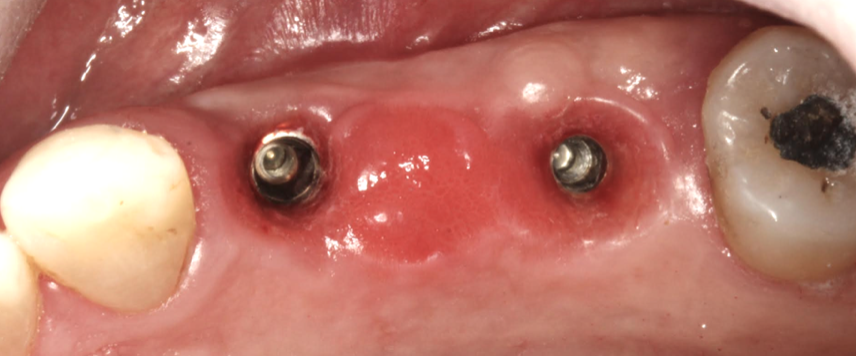

(3.) Prosthesis without access to the intaglio interface.

Figure 3

(4.) Intagilo inflammation of the soft tissue following removal of the prosthesis.

Figure 4

(5.) Prosthesis intaglio surface.

Figure 5

Several factors increasing the risk of peri-implantitis have been reported. Lack of access to the intaglio surface of the implant-supported prosthetics and poor oral hygiene of the implant is reported to increase the risk of peri-implantitis (Figure 3 through Figure 5). Concave intaglio design prevents oral hygiene access (Figure 6). Monje reported that 77.2% of the peri-implantitis cases had inadequate access for cleansability. 9 Serino and Ström found that 74% of the implants had no access to proper plaque control and highlighted the role of prosthesis design.10 Katafuchi suggested that a shallow emergence angle (EA) with a straight or concave transmucosal profile at the interproximal sites should be considered to minimize peri-implantitis risk for bone-level implant.11